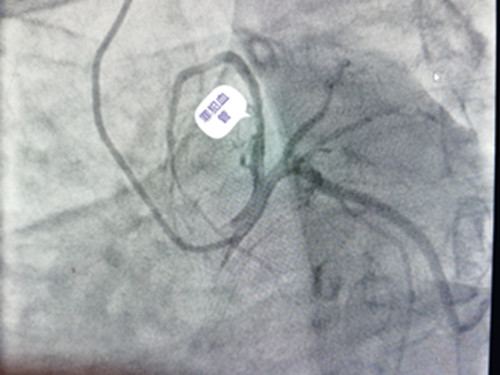

心内科是集医疗、教学为一体的综合科室。科室共有医护人员26人,主任医师1人,副主任医师2人,主治医师7人,硕士研究生4人。科室人员曾多次到北京协和医院、阜外医院、安贞医院等著名医院进修学习。科室人员业务素质过硬,技术力量雄厚,在长期从事心内科临床诊疗工作中,对治疗高血压病、冠心病、心绞痛、心肌梗死、心肌病、风湿性心脏病、心力衰竭、各种心律失常等方面经验丰富。目前本科能开展冠状动脉造影术和择期冠状动脉介入治疗(PCI)术、心内电生理检查、心律失常射频消融术,永久性心脏起搏器植入术等心脏介入诊疗技术,以及心脏永久起搏器的程控和随访。

科室配有先进的医疗设备:遥控心电监测仪、除颤仪、动态血压检测仪、动态心电检测仪、无创呼吸机等。心脏介入室配有美国GE大C臂平板血管造影(DSA)机,64排螺旋CT,心脏多导电生理记录仪, 主动脉内球囊反搏泵(IABP)等大型先进医疗设备。